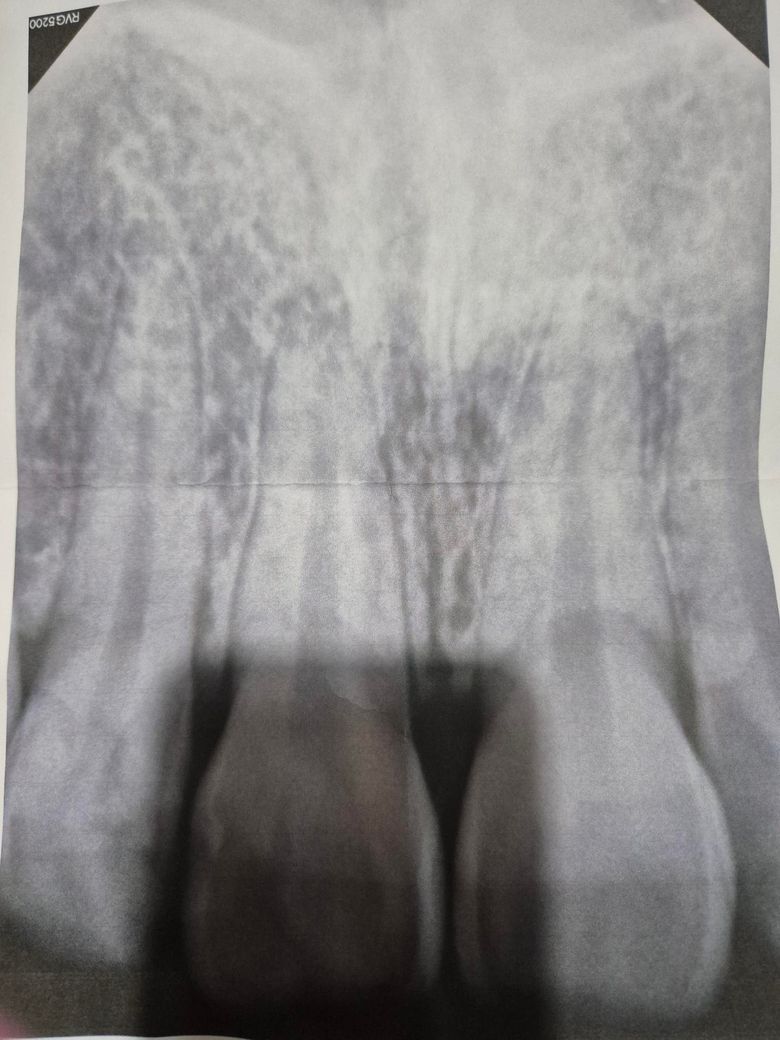

앞니가 깨져서 신경치료 2회 후 크라운씌우고, 치근단 염증제거 수술도 했습니다. 그리고 최근 외상으로 이빨이 흔들려서 치과 갔지만 거기서 사진도 안 찍어보고 2개월정도 기다리자고 하더라구요? 그래서 지켜봤는데, 더 흔들려서 엑스레이 찍어보니 뿌리 흡수가 진행중이라서 임플란트 밖에 답이 없다고 하더라구요. 그 옆에 앞니도 표면에 금이 갔는데, 이건 그냥 냅둬도 된다고도 하더라구요.

사진은 신경치료전(6월)->최근(10월) 입니다.

사진으로 보아서는 이미 신경치료 이후에 치근단절제술까지 한 것으로 보여집니다. 치아를 살릴 수 있는 모든 방법을 한 것으로 보여지며 계속해서 치아의 뿌리 흡수가 일어나고 그로 인하여 동요도(흔들림)이 발생한다면 결국 발치 이후에 임플란트나 브릿지로 넘어갈 수 밖에 없습니다. 과거 외상으로 치아가 손상되었다면 이러한 증상은 흔하게 나타납니다.

1. 염증성 치근 외흡수의 양상으로 보입니다

2. 꼭 외흡수가 있다고 임플란트를 해야하는건 아니지만 불편한 증상이 있다면 임플란트도 고민해봐야합니다